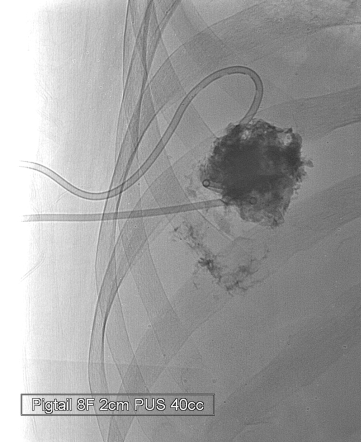

DS Liver Abscess Drainage : Right lateral intercostal space를 통하여 18G needle로 hepatic abscess을 천자하였고 guideiwre삽입함. Guidewire 따라 8.5F pigtail drainage catheter를 삽입함. Pus 40cc배액함.